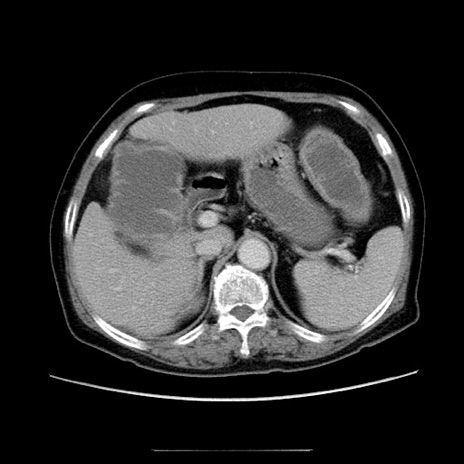

症例5(横断像)

【症例】70歳代女性

【主訴】お腹が張る

【現病歴】1週間くらい前から腹部膨満の自覚あり。昨日夜から増悪したため、本日救急外来受診。

【身体所見】意識清明、BT 36.5℃、BP 165/106mmHg、HR 80bpm、SpO2 98%、腹部:膨満、軟、自発痛・圧痛なし、触診にて不快感あり、腸蠕動音:減弱

【データ】WBC 12600、CRP 1.04